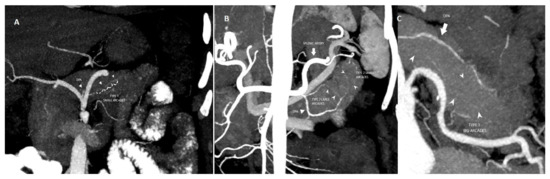

| Arcade Classification | p Value | |||

|---|---|---|---|---|

| Type 1 (n = 20) | Type 2 (n = 35) | Type 3 (n = 16) | ||

| POPF (+/−) | 4/16 | 9/26 | 9/7 | 0.042 |